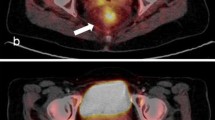

Of 123 patients, 26 (29.3 %) were classified as metabolic complete responders on visual analysis of late PET/CT images. Figures 1 and 2 show representative images of complete and incomplete metabolic responses, respectively. Radiation-induced inflammation on late PET/CT images, defined as the appearance of new 18F-FDG uptake in the radiation therapy field outside the tumour area on the baseline scan, was detected in 8 of 123 (6 %) patients. All of these patients met the criteria for qualitative assessment of treatment response.

18F-FDG PET/CT images in a patient with a complete pathological response. a Baseline images: intense 18F-FDG uptake is evident in a cT3 lesion (SUVmax 18.5). b Early images: a significant decrease in tumour SUVmax is evident (SUVmax 6.8; RI 63.2 %). c Late images: the tumour has completely disappeared (SUVmax 2.0; RI 89.2 %). Histopathological analysis after low anterior resection showed total tumour regression (ypT0 N0, TRG1). Neither local nor distant recurrence occurred during 36 months of follow-up

18F-FDG PET/CT images in a patient with non-complete pathological response. a Baseline images: intense 18F-FDG uptake is evident in a cT4 lesion (SUVmax 16.6). b Early images: a slight decrease in tumour SUVmax is evident (SUVmax 8.8; RI 46.9 %). c Late images: a further decrease in tumour SUVmax is evident (SUVmax 5.4; RI 67.5 %). Histopathological analysis after abdominoperineal resection showed ypT3N1, TRG3. Neither local nor distant recurrence occurred during 63 months of follow-up